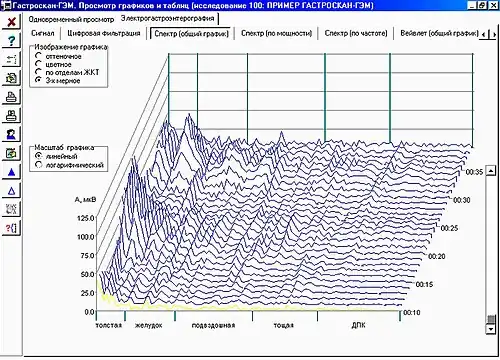

Электрогастроэнтерография

Электрогастроэнтерография основана на записи электрических потенциалов гладкомышечных органов ЖКТ. В клинической практике используют два варианта: электрогастрографию, когда оценивается сократительная активность только желудка и запись ведётся с поверхности живота[27][29] и периферическая электрогастроэнтерография, когда исследуется моторика не только желудка, но и кишечника, и запись ведётся с конечностей пациента[30][31]. Периферическая электрогастрография применяется при диагностике функциональной диспепсии, пилоробульбарного стеноза, спаечной болезни брюшной полости, мезентериального тромбоза. Для диагностики и коррекции моторно-эвакуаторной функции ЖКТ у пациентов, находящихся в реанимации в послеоперационный период, используется длительная электрогастроэнтерография (18—24 часа) с применением парентеральных стимуляторов (прокинетики, прозерин, дистигмина бромид) вместо пищевого[30].

- Периферическая электрогастроэнтерография

Двухканальный носимый суточный электрогастро-

Двухканальный носимый суточный электрогастро-

энтерограф Электрогастроэнтеро- грамма человека

Электрогастроэнтеро- грамма человека Космонавт Сергей Волков с прибором для электрогастроэнтерографии «Спланхограф» на борту Международной космической станции.

Космонавт Сергей Волков с прибором для электрогастроэнтерографии «Спланхограф» на борту Международной космической станции.

См. также